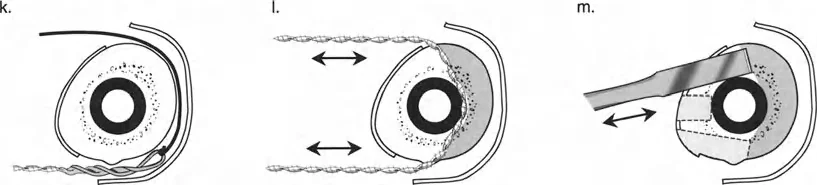

ومع ذلك، تعتمد هذه "المعجزة البيولوجية" بشكل كبير على الاستقرار الميكانيكي. إذا كان المثبت الخارجي شديد الصلابة، فقد لا يتكون العظم الجديد بشكل كافٍ؛ وإذا كان فضفاضًا جدًا، فإن قوى القص ستدمر الأوعية الدموية الدقيقة التي تتشكل في الفجوة، مما يؤدي إلى تكوين غضروف ليفي وعدم التحام العظم. يجب أن يوفر الجهاز حركة محورية دقيقة مع منع قوى القص وعدم الاستقرار الدوراني بشكل صارم.

قيود الأسلاك والدبابيس في القاعدة 2

لتحقيق هذه الترجمة الضرورية والمقصودة بسلاسة باستخدام إطار دائري كامل الأسلاك، يلزم استخدام أسلاك الزيتون المعاكسة (counter-opposed olive wires). تعمل أسلاك الزيتون كقوى سحب ديناميكية، تسحب قطعة العظم على طول الحلقة أثناء فتح المفصلات. بدون أسلاك الزيتون، سيبقى العظم ثابتًا بينما تتحرك الحلقة عبر الأنسجة الرخوة، مما يسبب نخرًا شديدًا في الجلد.

على العكس من ذلك، إذا تم استخدام دبابيس نصفية (مسامير شانز)، فإنها تقيد العظم بطبيعتها بالحلقة. نظرًا لأن الدبابيس النصفية هي أذرع صلبة (مثبتة من طرف واحد بالحلقة ومغروسة في العظم من الطرف الآخر)، فإنها لا تسمح للعظم بالانزلاق على طول محور السلك. هذا يجعل أسلاك الزيتون غير ضرورية للترجمة في منشآت الدبابيس النصفية، ولكنه يتطلب من الجراح التأكد من أن الدبابيس النصفية قوية بما يكفي (عادةً دبابيس بقطر 5 مم أو 6 مم مطلية بهيدروكسي أباتيت) لتحمل لحظات الانحناء الناتجة عن الترجمة.

إتقان معدلات الشد: قاعدة المثلثات المتشابهة

القاعدة الذهبية البيولوجية لتوليد العظم بالشد، التي وضعها إليزاروف بعد عقود من التجارب على الحيوانات والبشر، هي معدل شد يبلغ 1 ملم يوميًا. يتم تقسيم هذا عادة إلى زيادات قدرها 0.25 ملم كل 6 ساعات لمحاكاة النمو المستمر للوحة النمو.

ومع ذلك، فإن الخطأ الشائع، الذي قد يكون كارثيًا أحيانًا للجراحين المبتدئين، هو سوء فهم أين يجب أن يحدث هذا الـ 1 ملم يوميًا.

معدل 1 ملم/يوم ينطبق بشكل صارم على القشرة المقعرة للعظم في موقع قطع العظم (الحافة الأمامية للإسفين المفتوح). نظرًا لأن الجهاز (قضيب الشد أو دعامة TSF) يقع على مسافة من العظم، خارج غلاف الأنسجة الرخوة، فإنه يتحرك على طول قوس أكبر بكثير. إذا وجهت المريض لشد القضيب بمعدل 1 ملم يوميًا، فإن العظم الفعلي سيُشد بجزء ضئيل من هذا المعدل، مما يؤدي إلى التصلب المبكر لموقع قطع العظم.

حساب معدل الشد الحقيقي

لحساب المعدل الصحيح للشد عند المفصلة، نستخدم قاعدة المثلثات المتشابهة، والتي تعتمد أساسًا على القاعدة الهندسية للدوائر متحدة